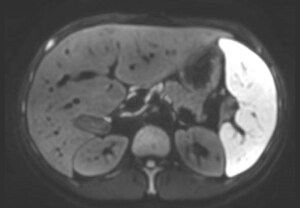

La excelente capacidad de eliminación de ruido de SmartSpeed de Philips permite obtener imágenes con una resolución extremadamente alta sin aumentar el tiempo de adquisición. Esto es especialmente importante, por ejemplo, para representar lesiones pequeñas en el sistema vascular".

Takashige Yoshida, Ph.D.,

Hospital Metropolitano de la Policía de Tokio, Japón